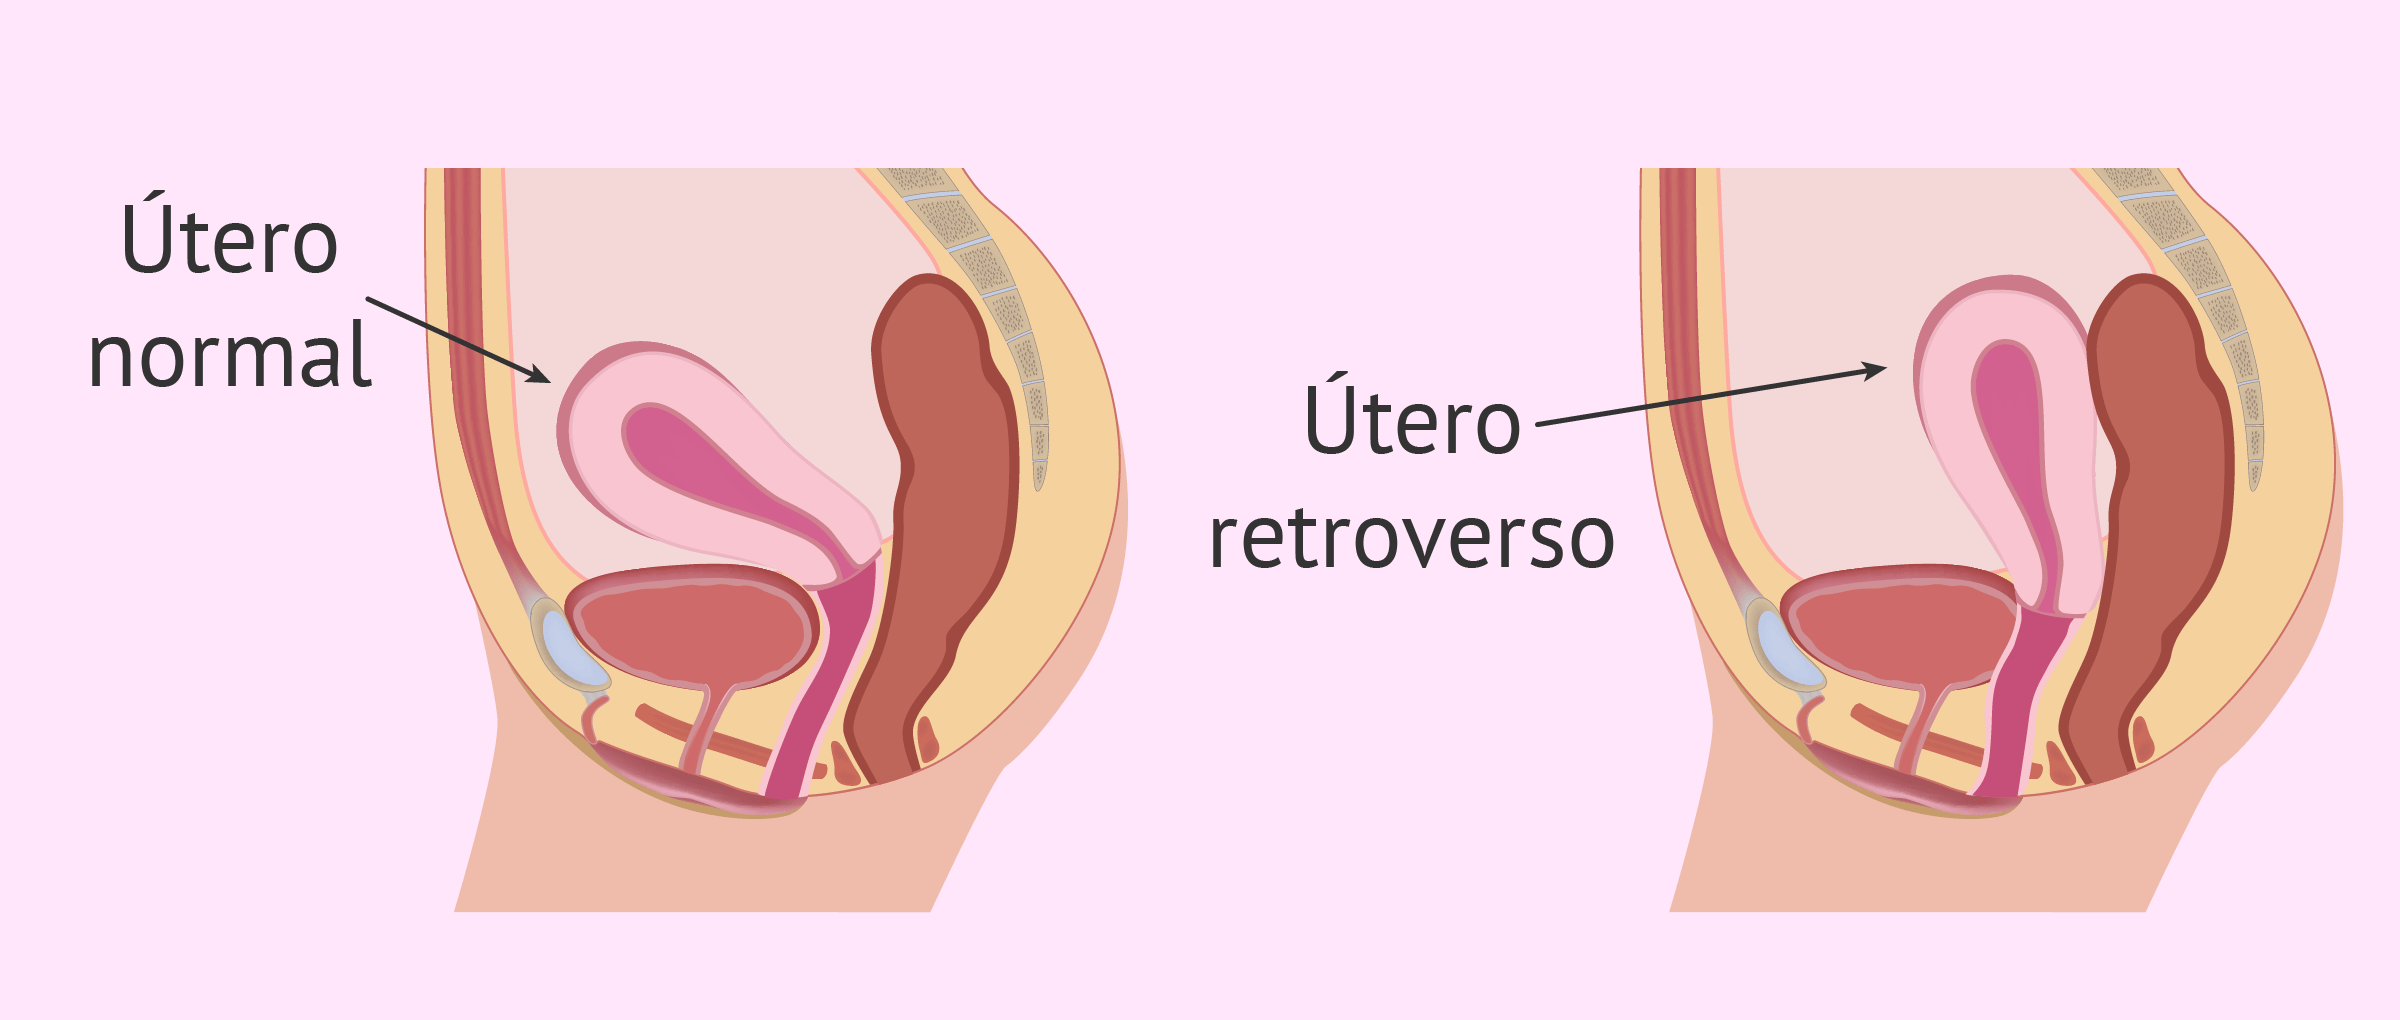

- Non hai un utero

- Hai problemi con il tuo utero

- Non puoi portare avanti una gravidanza in modo sicuro